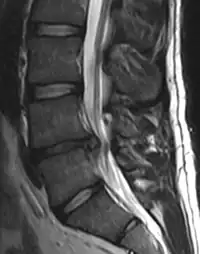

A herniated disc as seen on MRI, one possible cause of low back pain